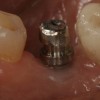

The altered, color-corrected abutment is then placed onto the implant fixture and torqued to the implant manufacturer’s recommendation. From an occlusal view, any gingival tissue that obstructs the margin of the abutment must be removed, preferably with the use of a diode laser. Placing block-out material into the screw-access hole of the abutment is not advised. Whether a CAD/CAM chairside system is used or a traditional impression technique is employed, leaving the screw-access hole open on the abutment will create a positive mark on the undersurface of the milled crown (Figure 5). This will aid in the precise placement of the screw-access hole. The steps in fabricating a CAD/CAM crown can be completed.

Fig 5. The scanned image of the abutment with the clearly defined screw-access hole.

Figure 5